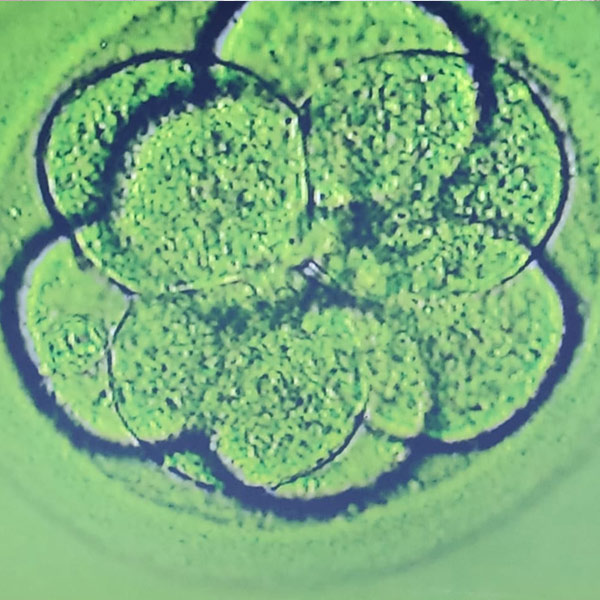

• Fertilization: The retrieved eggs and sperm are combined in a laboratory dish. Fertilization occurs, forming embryos.